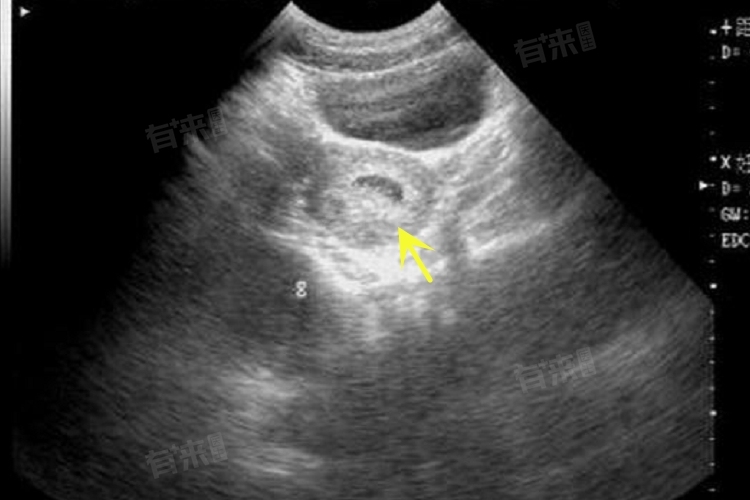

- 5代表囊胚处于孵化中囊胚阶段,此时囊胚已经开始从透明带中孵出,意味着发育程度相对较高,有一定的活力和着床潜力。b表示内细胞团细胞数目较少,排列松散。内细胞团将来会发育成胎儿的各种组织和器官,细胞数目少且排列松散,说明发育成胎儿主体结构的能力相对较弱。

- c表示滋养层细胞上皮细胞层由稀疏的细胞组成,滋养层细胞主要形成胎盘和胎膜等结构,为胚胎发育提供营养支持,稀疏的细胞组成可能会影响其功能的发挥。与更优质的囊胚如5aa、5ab相比,5bc的囊胚在细胞数量和排列上存在差距,移植后的着床率和妊娠成功率相对较低。但相较于更低等级的囊胚,又具有一定的优势,并非完全没有成功着床的可能。

在辅助生殖领域,囊胚评级是评估胚胎质量的重要依据,5bc的囊胚,虽在细胞数量、滋养层细胞形态等方面并非最优质,但其仍具备一定的发育潜能。在无更优胚胎可选时,可谨慎考虑移植。最终能否成功着床和正常发育,受女性身体激素水平、子宫内膜厚度及容受性等多种因素综合影响。